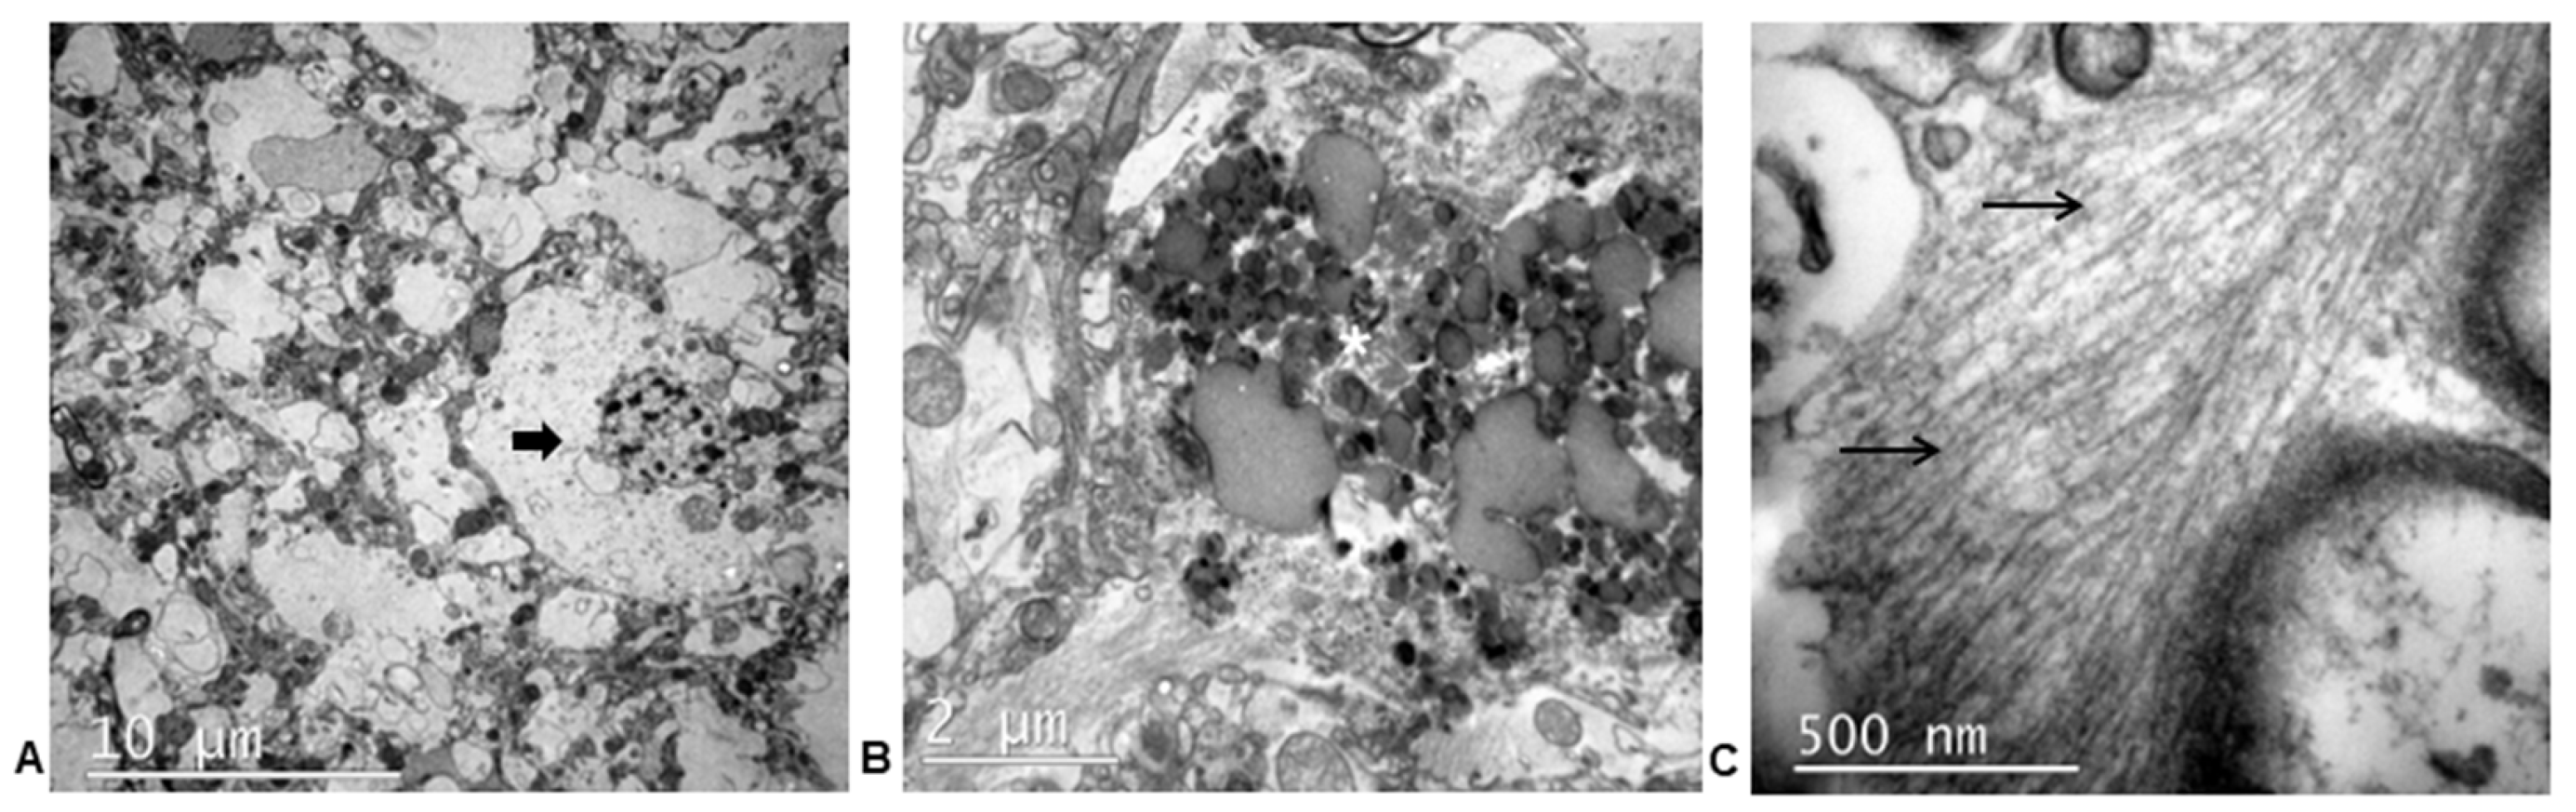

3.3.3. Ultrastructural Study